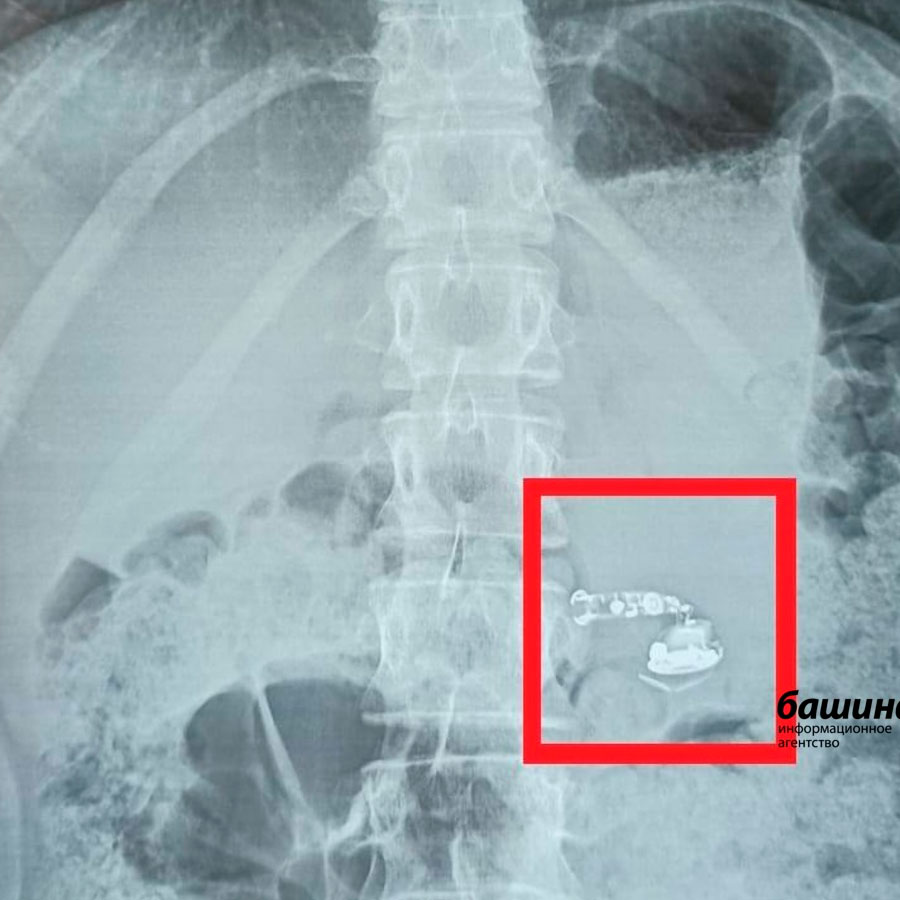

Вот вам загадка. Что объединяет все предметы на фото?

Правильно. Все их в разное время "вытищили" из маленьких пациентов в Башкирии.

Монеты, магнитные шарики, зубочистка, два гвоздя, игрушка из киндера, магнитная рыбка, наушники, заколка...иногда удивительно что может проглотить ребенок.